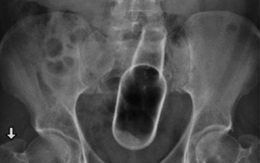

Khó tin: Nhét dây tai nghe điện thoại, đẩy hành lá, đút ly thủy tinh... vào chỗ kín

Mới đây, Bệnh viện Đa khoa tỉnh Tiền Giang tiếp nhận bệnh nhân tên C. (17 tuổi, ngụ thị xã Cai Lậy, tỉnh Tiền Giang) từ tuyến dưới chuyển lên trong tình trạng tiểu gắt, đau vùng bụng dưới với chẩn đoán dị vật bàng quang do thủ dâm.